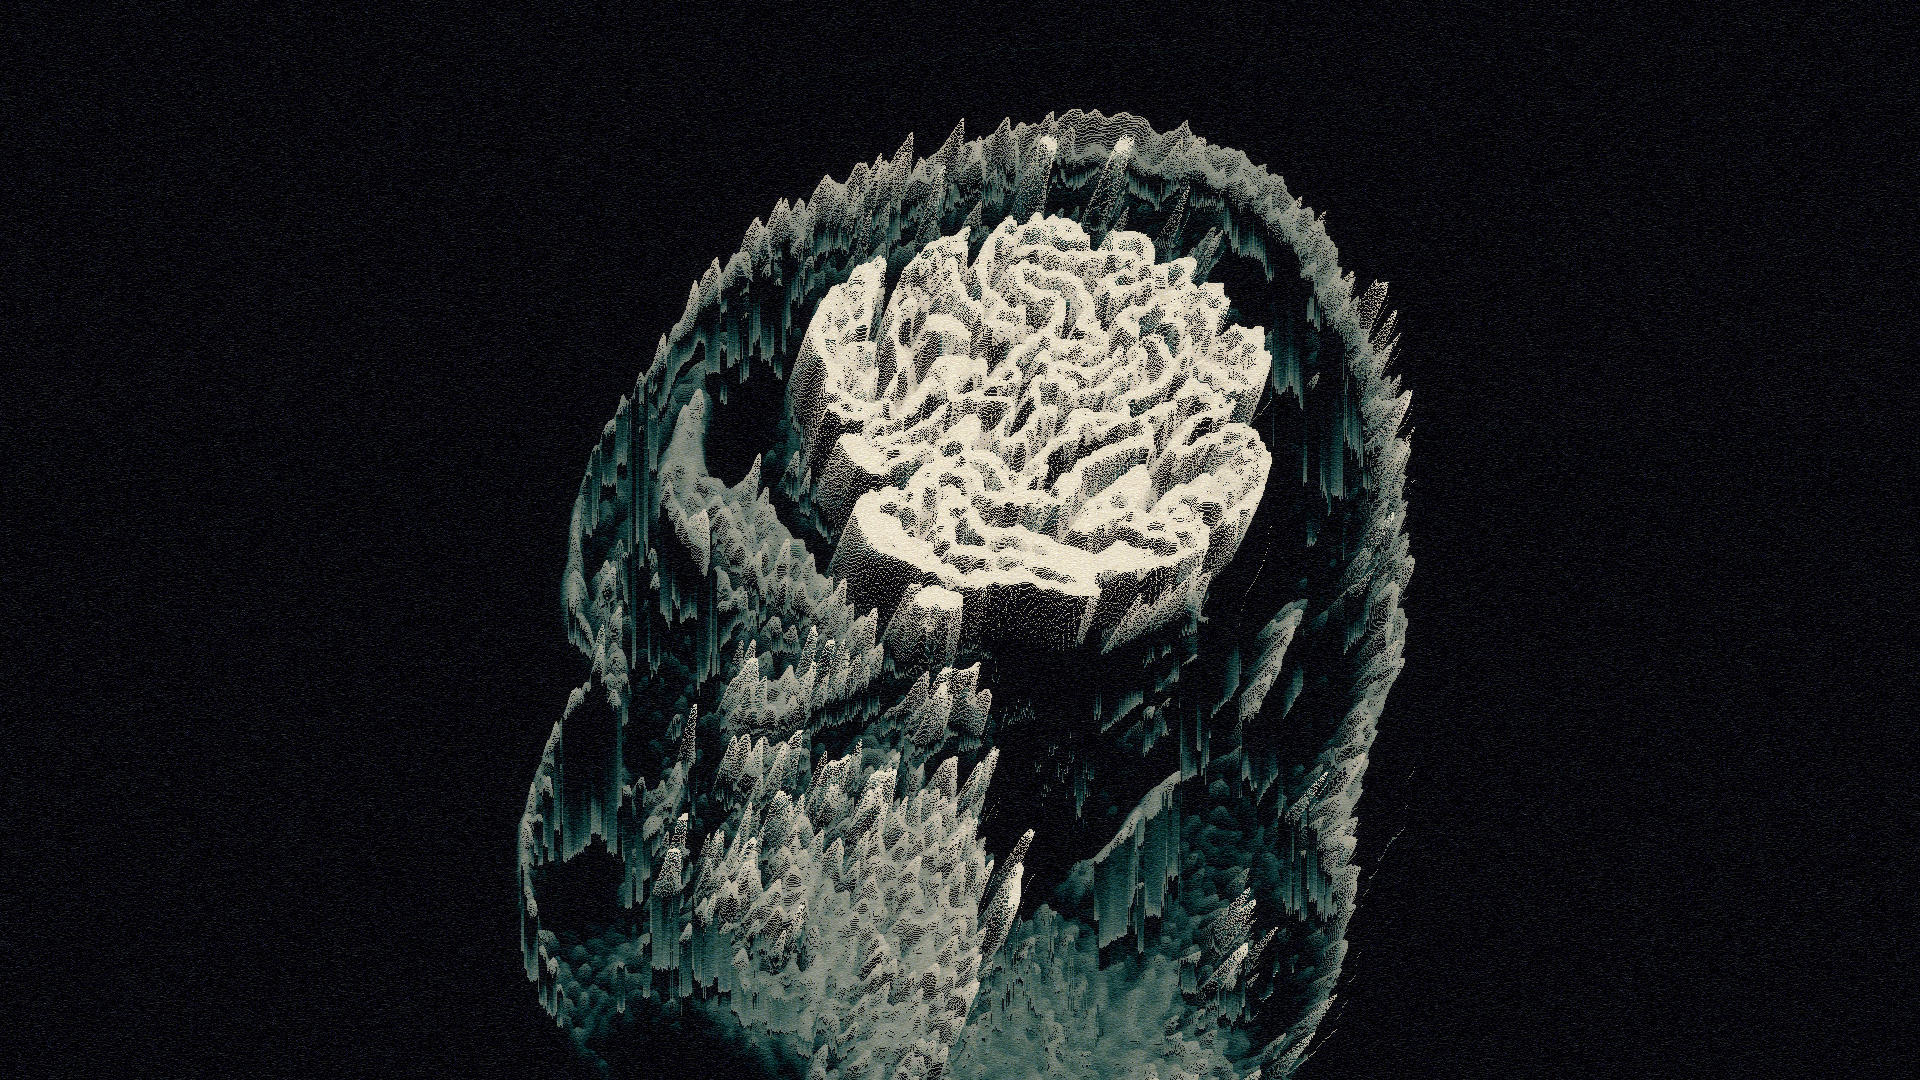

I recently developed style frames and animations for a television commercial. The main topic of the ad was to reflect Alzheimer's disease and what happened in the patient's brain.